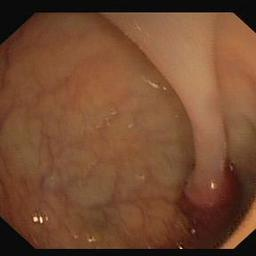

Medical image segmentation is a primary task in many applications, and the accuracy of the segmentation is a necessity. Recently, many deep learning networks derived from U-Net have been extensively used and have achieved notable results. To further improve and refine the performance of U-Net, parallel decoders along with mask prediction decoder have been carried out and have shown significant improvement with additional advantages. In our work, we utilize the advantages of using a combination of contour and distance map as regularizers. In turn, we propose a novel architecture Psi-Net with a single encoder and three parallel decoders, one decoder to learn the mask and other two to learn the auxiliary tasks of contour detection and distance map estimation. The learning of these auxiliary tasks helps in capturing the shape and boundary. We also propose a new joint loss function for the proposed architecture. The loss function consists of a weighted combination of Negative likelihood and Mean Square Error loss. We have used two publicly available datasets: 1) Origa dataset for the task of optic cup and disc segmentation and 2) Endovis segment dataset for the task of polyp segmentation to evaluate our model. We have conducted extensive experiments using our network to show our model gives better results in terms of segmentation, boundary and shape metrics.